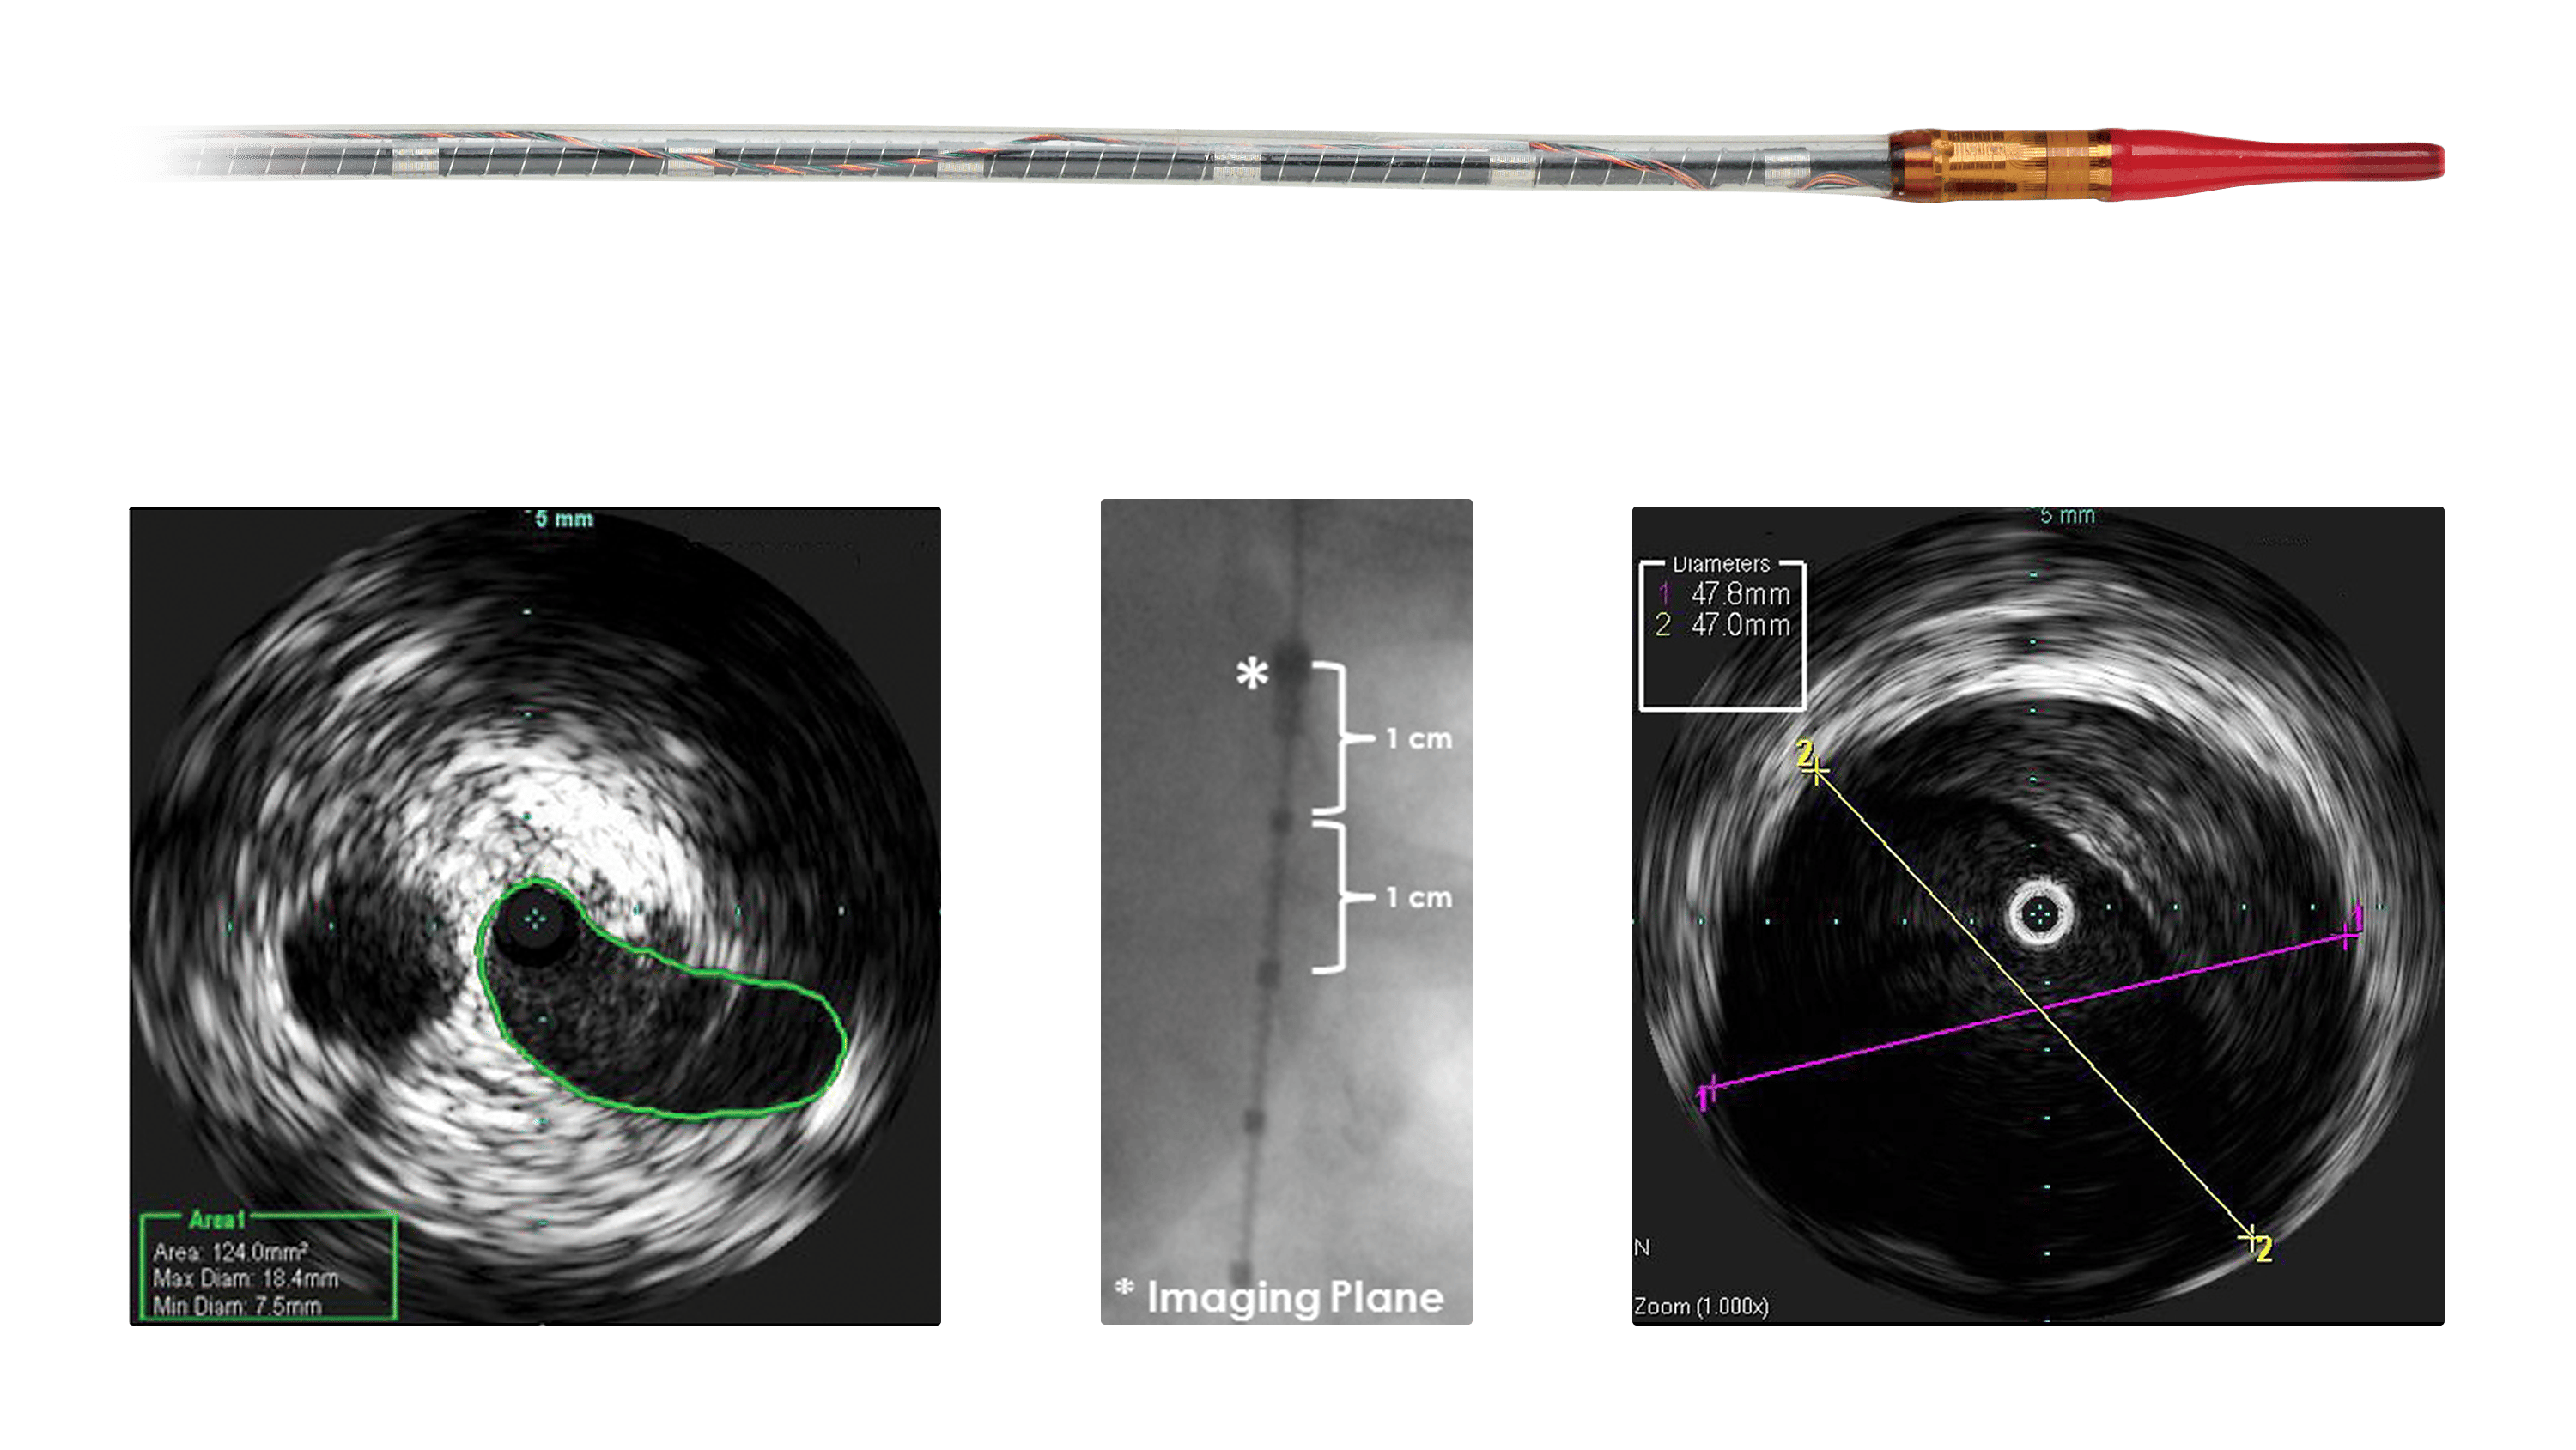

Visions PV (0,035 ДЮЙМА) — катетер ВСУЗИ

Периферический цифровой IVUS-катетер Philips Visions PV 0,035″ для визуализации крупных сосудов (аорта, подвздошные артерии). Фазированная решётка, ~20 МГц, максимальный диаметр визуализации 60 мм. Профиль 8,2 Fr в зоне датчика, ствол 7,0 Fr, рабочая длина 90 см. Совместимость с проводником 0.035″–0.038″, интродьюсер от 8,5F. GlyDx гидрофильное покрытие. Применение при EVAR/TEVAR. РЗН 2017/5858.